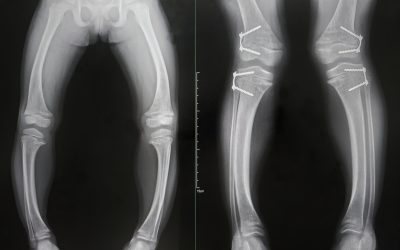

Osteomalacija je proces kod kojeg dolazi do omekšavanja kostiju i njihovog slabljenja zbog pomanjkanja vitamina D u organizmu ili pak zbog njegove poremećene apsorpcije. Vitamin D je vrlo bitan tijelu

Rahitis se opisuje kao dječja bolest kostiju. Ovaj naziv zapravo obuhvaća skupinu bolesti koje nastaju radi poremećaja mineralizacije, točnije ulaganja kalcija u hrskavičnu tvar kostiju koje su još u